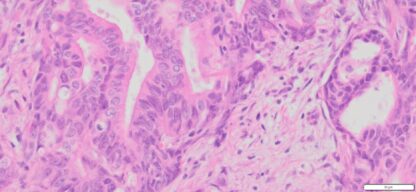

Description

| Tissue | Pathology Diagnosis | Gender/Age (year) | % Tumor area | Tumor Grade | TMN Stage | IHC Data |

| Human Colon | Colon moderately differentiated adenocarcinoma | Female/67 | 35% | II | pT4apN2pM1c | NA |

Images for H&E Stain and IHC